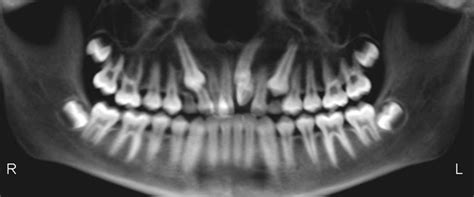

Radiografía panorámica mostrando dientes supernumerarios en el arco superior.

Un diente supernumerario es una pieza dentaria adicional a la formula normal (20 dientes en la dentición temporal y 32 en la permanentes). Puede presentarse en las diferentes etapas del desarrollo humano, tanto en la dentición temporal como en la mixta y permanente; constituyen uno de los factores que se asocian a la etiología de las maloclusiones y ocasionan alteraciones en la línea media, retención de piezas dentarias, apiñamientos, resorción radicular, diastemas y malformación de otros dientes. Se encuentran en cualquier región de la arco y sólo se pueden visualizar radiográficamente.

El diagnóstico temprano de los dientes supernumerarios es importante para evitar que se presenten complicaciones. Éste puede realizarse a través de la exploración clínica y radiográfica y su tratamiento dependerá de la posición y clase de supernumerario, así como el efecto sobre el diente temporal o permanente.